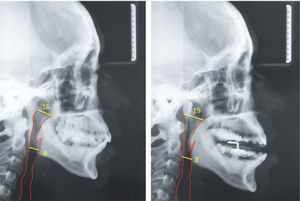

Casos clínicosSe muestran 2 pacientes que utilizaron un dispositivo de avance mandibular de diseño nacional, hecho en laboratorio Ortolab, durante 1 mes, donde previo y posterior al uso de este aparato se mide el índice de Apnea e Hipoapnea, ronquidos y saturación de oxígeno con el Apnealink®, de la empresa Resmed. Cada paciente presenta una polisomnografía inicial, 2 telerradiografías de perfil (con y sin el dispositivo) y distintos cuestionarios, Escala de Epworth, Escala de Thornton del sueño y Observador del sueño, respondidos antes y después del tratamiento.